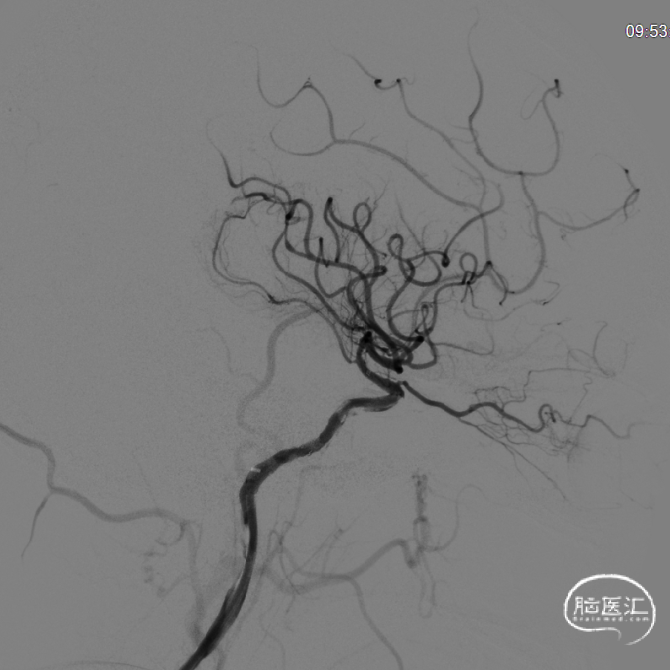

术前DSA:左侧颈内动脉起始段闭塞,可见残端,左侧颈外动脉经眼动脉向左侧颈内动脉供血区部分代偿,可见逆流至海绵窦段,左侧大脑后动脉经软脑膜向左侧大脑中动脉供血区代偿;右侧颈内动脉起始部中度狭窄(40%);右侧椎动脉开口重度狭窄(70%);右侧锁骨下动脉肋颈干开口以远处轻度狭窄;左椎动脉开口中度狭窄。

将4.0*39mm ENTERPRISE 2支架于颈内动脉释放并充分覆盖病变段,行正侧位造影示前向血流改善,mTICI分级3级。